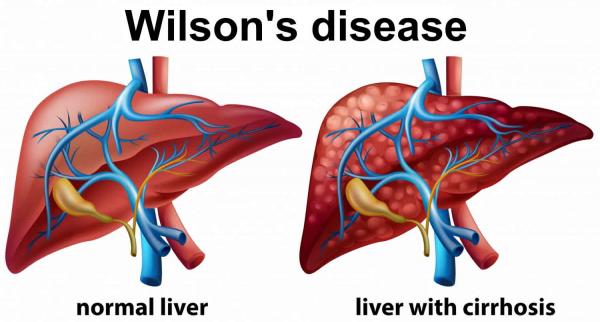

قیمت: 45٬000 تومان - دسته بندی فایل: پاورپوینتدانلود پاورپوینت شناخت بیماری ویلسون کبد

جدیدترین و ارزانترین فایل پاورپوینت با عنوان پاورپوینت شناخت بیماری ویلسون کبد تعداد اسلاید: 24